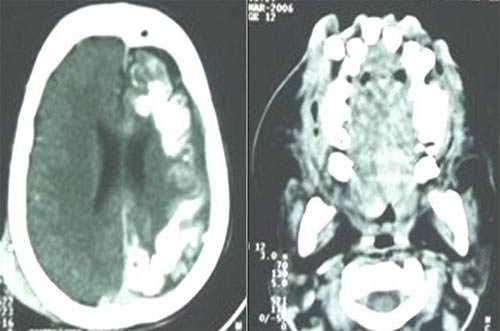

Paciente del género masculino de 8 años de edad, se presentó al servicio de Neurocirugía y Cirugía Buco Maxilofacial del Hospital Governador João Alves Filhos (H.G.J.A.F.), Aracaju/SE, Brasil. El enfermo manifestó que sufría de frecuentes crisis convulsivas y reducción de la agudeza visual. La progenitora afirmó que al nacer, el niño presentaba manchas en la cara, aumentando con el pasar de los años y el desarrollo físico del niño; relató no haber otro caso idéntico en la familia, autorizándonos a divulgar el caso clínico. En el examen clínico extrabucal se notó déficit neurológico, aumento de volumen maxilofacial, denotando el aspecto de "cara de elefante", com presencia de nevus flammeus, siguiendo toda región inervada por el nervio trigémino (V1/V2/V3), bilateralmente (Fig 01). Al examen intrabucal se observó severa hiperplasia de la encía, sangrante al toque, estando los dientes recubiertos por el tejido (Fig. 02). Se procedió al examen imagenológico, a través de la tomografía computarizada, revelando la presencia de displasia microvenular leptomeníngea, determinando la extensión, y confirmando el diagnóstico de Síndrome de Sturge-Weber, siendo posible la visualización de calcificaciones parenquimatosas y unidades dentales ectópicas (Fig. 03). El paciente fue sometido a evaluación por el Servicio de Oftalmología de la mencionada Unidad hospitalaria, siendo diagnosticado el glaucoma, confirmando la reducción en la agudeza visual. El tratamiento sugerido fue el control de las crisis convulsivas, utilizándose fármacos anticonvulsionantes, reduciendose la crisis de aparición de los episodios epilépticos, sin agravar la lesión hemangiomatosa de las encías.

Fig.3

Tomografía computarizada en corte axial, denotando la presencia de displasia micro-venular

leptomeníngea y calcificaciones parenquiomatosas y algunas unidades ectópicas dentales..

Los exámenes imagenológicos son fundamentales para la identificación de la displasia micro-venular leptomeníngea, determinando su extensión, y confirmando el diagnóstico de SSW (26). Las calcificaciones parenquimatosas presentadas a través de la tomografía computarizada, son las primeras manifestaciones imagenológicas en el SSW, característicamente descrita en la radiología convencional como calcificaciones piriformes en "línea de tranvía" (2).